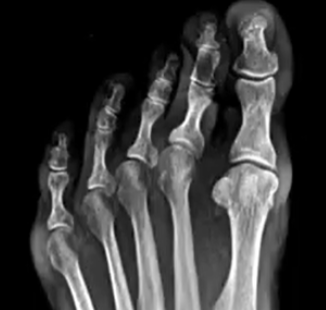

Let me see. These are from a set of videos online by a deceased podiatrist named Don Peacock. He did them as MIS in the office. I've watched almost all of his stuff - its all MIS burr. Some of them he says some stuff I don't agree with, but some of his other stuff is interesting, and the big thing to me is - I would have told that patient I had nothing to offer them. I feel like most people would have done PIPJ fusion + pinning + capsulotomy of MPJ + Weil - maybe they would have looked at the midfoot or rearfoot for deformity to see what's driving it / is it fixable. This was just eye turning to me because of how different it is from how I think about these. Would I do this on a 20 year old? Probably not - but a 60 year old with an end stage deformity ... seems like there's something to be said for it.

This is the video for the above x-rays and images:

-Yeah - no post-op - the final clinical image above was at 3 years.